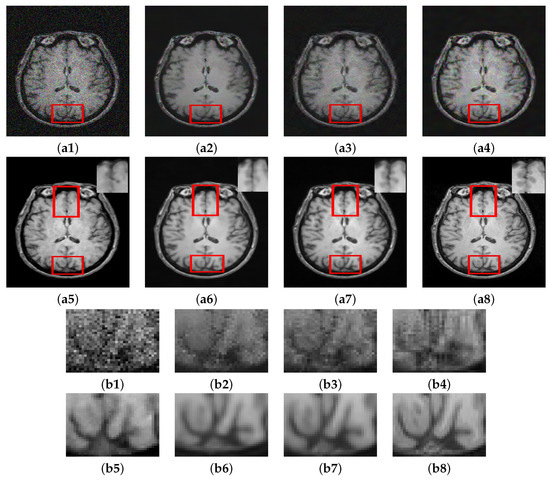

Another experiment (Experiment II) was conducted on the HH dataset using 13% noise. The denoising results are shown in Figure 8 along with enlarged regions for careful inspection. Table 6 shows the quantitative assessment results on different variants of data (i.e., registered and unregistered) using two different loss functions. Among the variants of the proposed method, it is observed that registration between the corresponding T1 and T2 images together with employing SSIM as loss function with MSE facilitates in improving the structural similarity between denoised image and ground truth as implied by the higher SSIM values in the case of C M G D N e t s g compared to its corresponding variants C M G D N e t r s and C M G D N e t s s ; however, noticeable improvement in PSNR values was not observed under this configuration.

To better understand the motivation of using cross-modal guidance information, the guidance image was bypassed and a noisy T1 image was fed to both branches of the PHL module as explained in Section 3.4. The results of this setup and its comparison with other variants of the proposed method are shown in Figure 9. Visually, the denoised images are similar on the whole; however, the enlarged ROI shows slight structural differences among the results. The model trained using identical noisy images fed to both branches (without guidance image) fails to recover various structures of the input image. Both C M G D N e t r s and C M G D N e t s s yield better results compared to the T1-T1 configuration; however, they also lack in recovering some structural information. C M G D N e t r g shows better performance compared to the three variants in terms of retaining structural similarity with the ground truth. Incorporating SSIM in the registered configuration, that is C M G D N e t s g configuration performs best. It not only retains structural similarity to a considerable extent, moreover, it also gives sharp edges compared to all the other variants. The PSNR-SSIM values for all the configurations tested are shown in Table 7.

Figure 8. Role of using cross-modal guidance information in denoising: Results of C M G D N e t method (a1) Noisy. (a2) Unreg. T2. (a3) Reg. T2. (a4) T1-T1. (a5) C M G D N e t r s . (a6) C M G D N e t s s . (a7) C M G D N e t r g . (a8) C M G D N e t s g . (a9) GT, Corresponding enlarged ROI (b1) Noisy. (b2) T1-T1. (b3) C M G D N e t r s . (b4) C M G D N e t s s . (b5) C M G D N e t r g . (b6) C M G D N e t s g . (b7) GT.